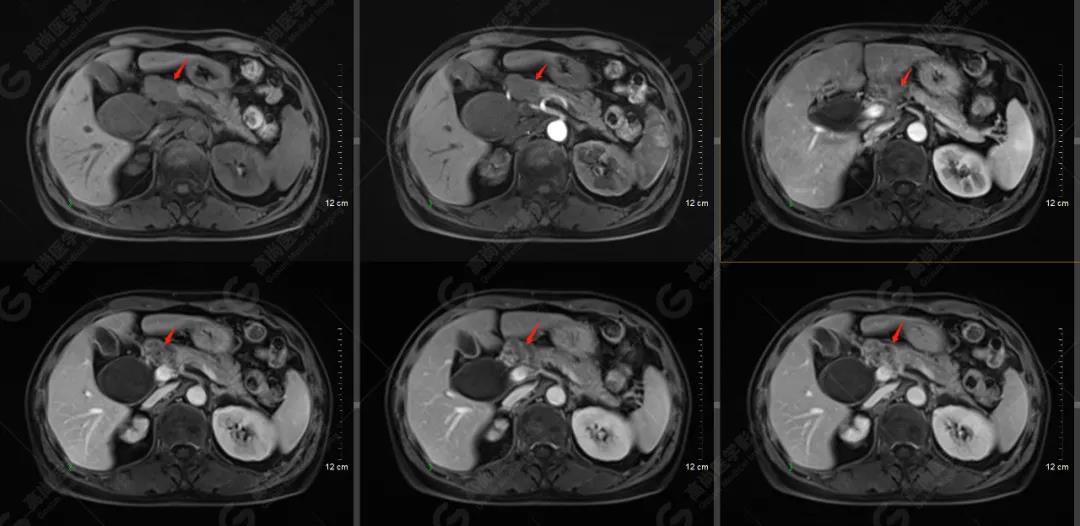

其他影像檢查

MR檢查所見:胰頭可見結(jié)節(jié)狀異常信號影,大小約2.5×1.8cm,T1WI呈稍低信號,T2WI呈略高信號,信號欠均勻,DWI可見彌散受限,病灶與周圍正常胰腺組織分界欠清,Gd-DTPA增強(qiáng)掃描病灶呈明顯不均勻強(qiáng)化;病灶相應(yīng)節(jié)段上方膽總管明顯囊腫擴(kuò)張,大小約6.4×4.0cm。肝內(nèi)膽管輕度不均勻擴(kuò)張,以左支為著,呈軟藤征。胰管未見擴(kuò)張。胰頭上緣及腹膜后(腹主動脈旁)見腫大淋巴結(jié),增強(qiáng)掃描可見中度強(qiáng)化,部分強(qiáng)化不均勻;腹腔未見積液。

提示: 胰頭占位性病變,性質(zhì)考慮為胰腺癌并胰頭上緣、腹膜后多發(fā)淋巴結(jié)轉(zhuǎn)移

肝內(nèi)膽管輕度擴(kuò)張,膽總管囊狀擴(kuò)張